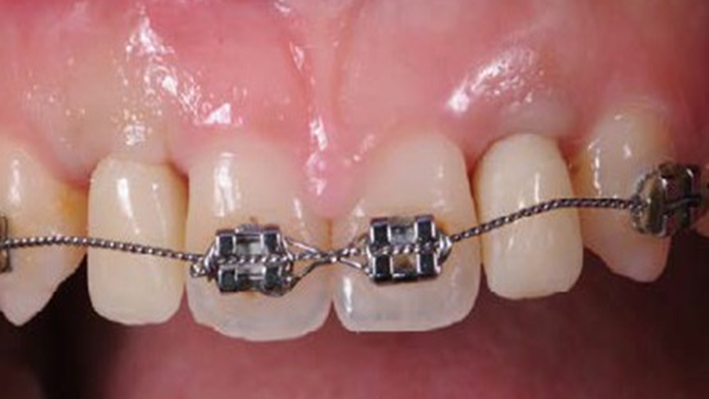

Clinical case: Patient-centered approach: treatment strategy for Root Membrane Technique & delayed implant placement

- Courtesy of Dr. Yoshiharu Hayashi, Japan -

Socket Shield Technique, anterior esthetics, maxillary anterior, esthetic, esthetics, delayed implant placement, socket preservation, AnyRidge, Root Membrane Kit, Root Membrane Technique, Partial Extraction Therapy, PET, esthetic zone, fuse abutment, Dr. Yoshiharu Hayashi,#11,#21,#22

Products:

AnyRidge implant system, fuse abutment Root membrane kit, PET Kit